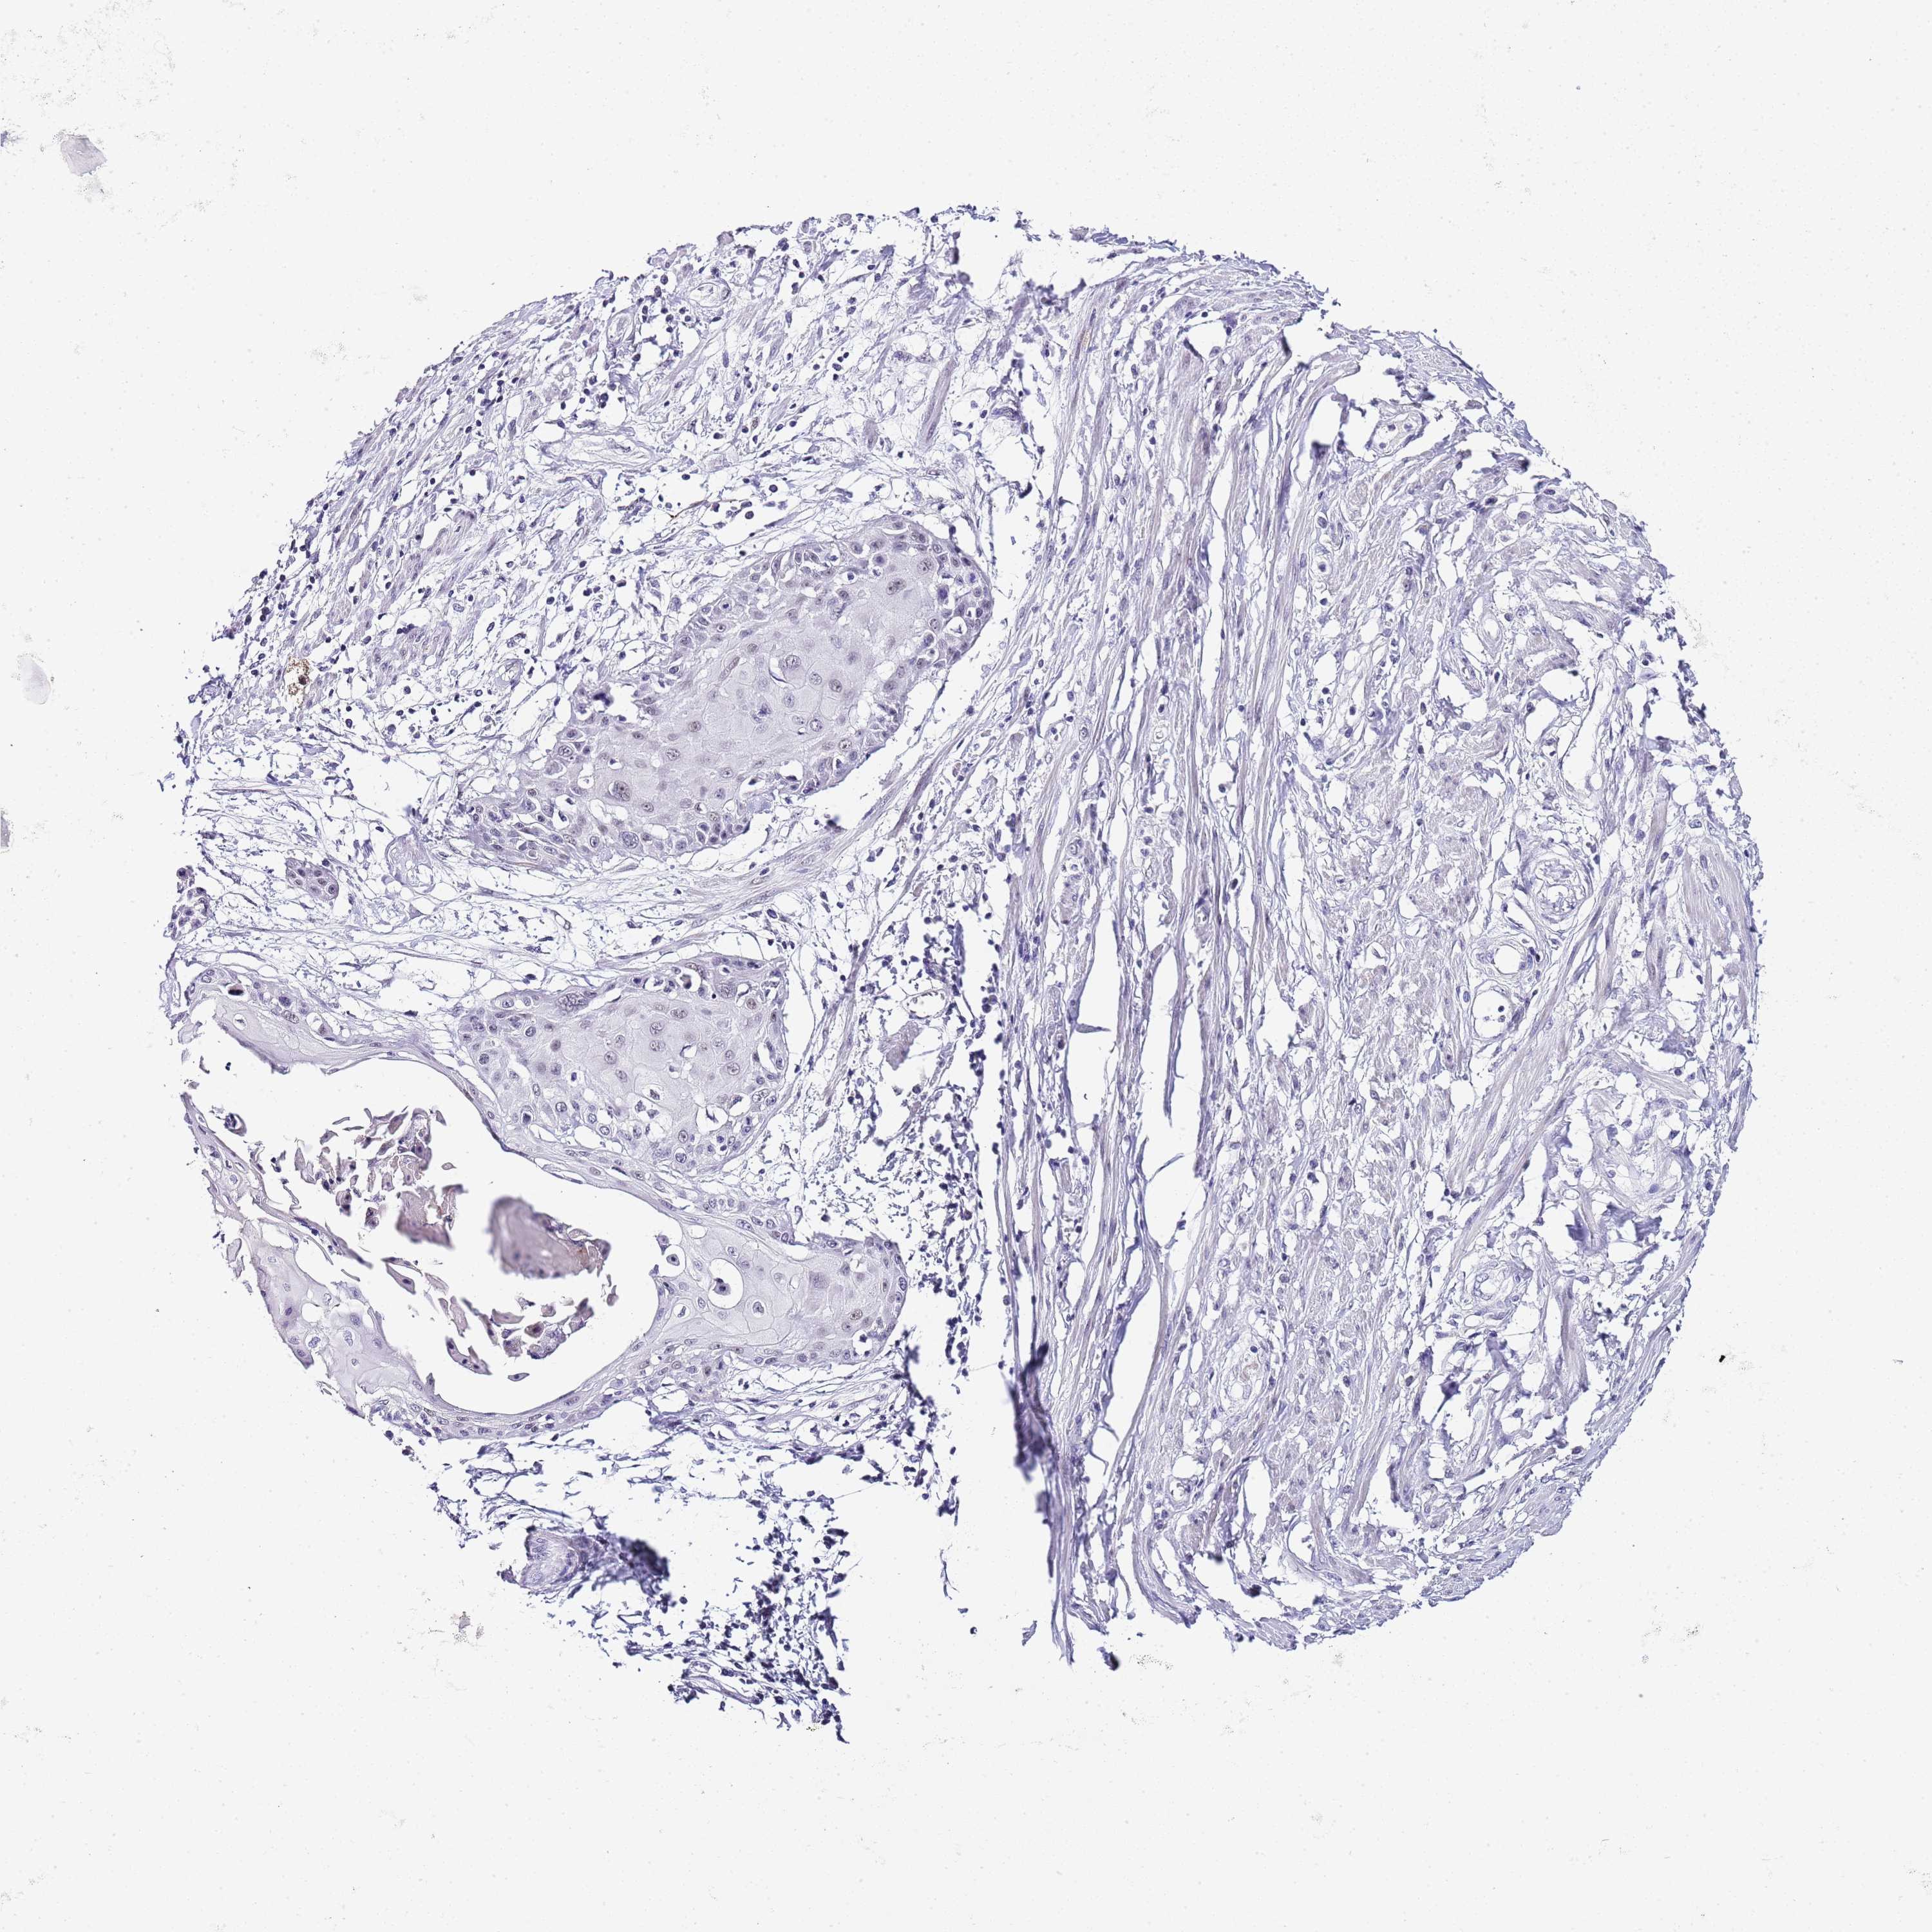

CERVICAL CANCER - Protein expressioni

A mouse-over function shows sample information and annotation data. Click on an image to view it in a full screen mode. Samples can be filtered based on level of antibody staining by selecting one or several of the following categories: high, medium, low and not detected. The assay and annotation is described here.

Note that samples used for immunohistochemistry by the Human Protein Atlas do not correspond to samples in the TCGA dataset.

Antibody stainingi

Antibody staining in the annotated cell types in the current human tissue is reported as not detected, low, medium, or high, based on conventional immunohistochemistry profiling in selected tissues. This score is based on the combination of the staining intensity and fraction of stained cells.

Each image is clickable and will lead to virtual microscopy that enables deeper exploration of all samples and also displays staining intensity scores, fraction scores and subcellular localization as well as patient and tissue information for each sample.

Antibody CAB075757

Staining

High

Medium

Low

Not detected

Intensity

Strong

Moderate

Weak

Negative

Quantity

>75%

75%-25%

<25%

None

Location

Nuclear

Cytoplasmic/membranous

Cytoplasmic/membranous,nuclear

Adenocarcinoma, NOS